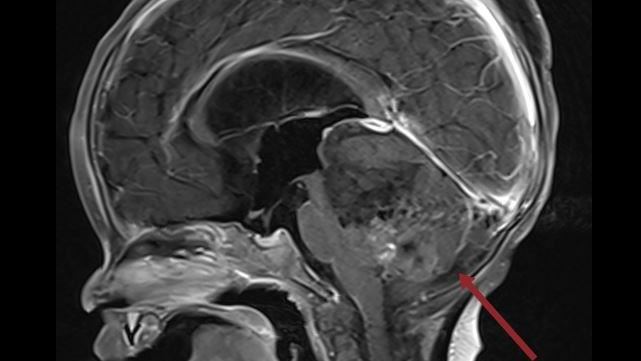

▲該病童手術前。(圖/北醫附醫提供)

打破傳統放射治療年齡限制!一名才9個月大的小嬰兒,罹患非常罕見的惡性腦瘤「非典型畸胎橫紋肌樣瘤」(ATRT),就醫檢查發現腫瘤幾乎佔滿病童的後顱窩中央,治療難度極高,還得分兩次手術切除。所幸搭配腫瘤部位質子及藥物治療,讓該病童恢復良好。

北醫大兒童腦瘤團隊召集人黃棣棟教授表示,ATRT是非常罕見的惡性腦瘤,通常好發3歲以下幼童,台灣平均2年約有2例,而台北癌症中心2022年8月收治該病童時僅9個月大,當時腫瘤幾乎佔滿病童的後顱窩的中央部分,由於難度高,必須分兩次手術切除,所幸手術順利,之後再搭配腫瘤部位質子及藥物治療,讓該名病童恢復良好。